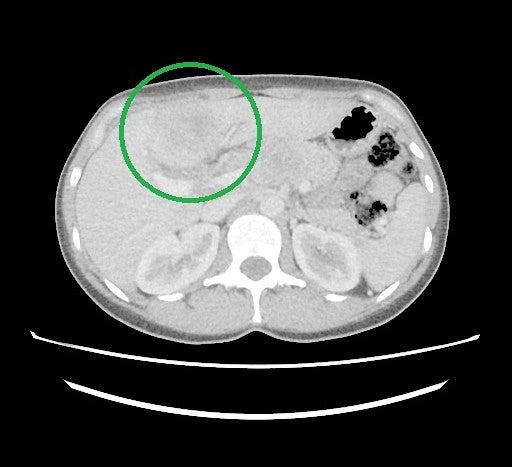

1/2025 MRCP s nejasným ložiskem SIVb jater velikosti 55x42x47 mm

Obr. 1: MRCP s nejasným ložiskem SIVb jater velikosti 55x42x47 mm